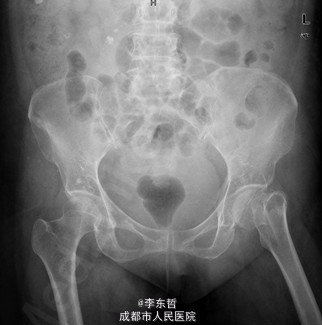

患者女,61岁,因“摔伤致左髋疼痛伴活动受限4+天”入院。患者自诉4+天前在浴室里不慎滑倒,左髋部着地,当时感左髋部剧痛,伴有活动受限,不伴有恶心呕吐、头痛头昏等不适。患者随即被家属送至当地医院,完善X线片后提示左股骨颈骨折,给予对症支持治疗后,患者家属为求进一步诊治,转至我院急诊科,以左股骨颈骨折送入我科。

查体:T:37.2oC,P:96次/分,R:22次/分,BP:113/62mmHg。神志清楚,无病容,皮肤巩膜无黄染,全身浅表淋巴结未见肿大。颈静脉正常。心界正常,心律齐,各瓣膜区未闻及杂音。胸廓未见异常,双肺叩诊呈清音,双肺呼吸音清,未闻及干湿啰音及胸膜摩擦音。腹部外形正常,全腹柔软,无压痛及反跳痛,腹部未触及包块,肝脏肋下未触及,脾脏肋下未触及,双肾未触及。双下肢无水肿。专科查体:视:双下肢不等长,左下肢外旋畸形,左髋肿胀,周围皮肤未见红肿,溃疡,窦道,瘘管等形成;触:双下肢皮肤感觉正常,末梢循环良好,足背动脉可扪及,左髋肿胀,触压痛明显,股骨颈叩击痛阳性,未闻及骨摩擦音及摩擦感;动量:双下肢肌力及肌张力正常,右髋、双膝、踝关节活动度良好,左下肢较右侧缩短约2cm,左髋因疼痛拒动。 辅助检查X片示:左股骨颈骨折,远断端向上方错位,左髋关节在位。骨盆骨质疏松。